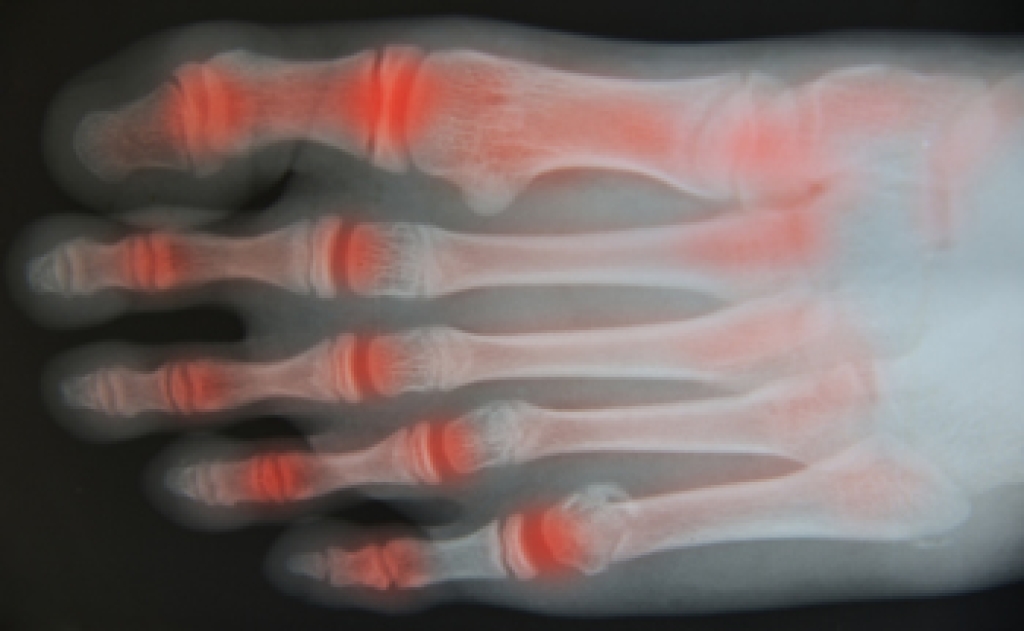

Podiatric biomechanics is a particular sector of specialty podiatry with licensed practitioners who are trained to diagnose and treat conditions affecting the foot, ankle and lower leg. Biomechanics deals with the forces that act against the body, causing an interference with the biological structures. It focuses on the movement of the ankle, the foot and the forces that interact with them.

Modern technological improvements are based on past theories and therapeutic processes that provide a better understanding of podiatric concepts for biomechanics. Computers can provide accurate information about the forces and patterns of the feet and lower legs.

Understanding biomechanics of the feet can help improve and eliminate pain, stopping further stress to the foot.